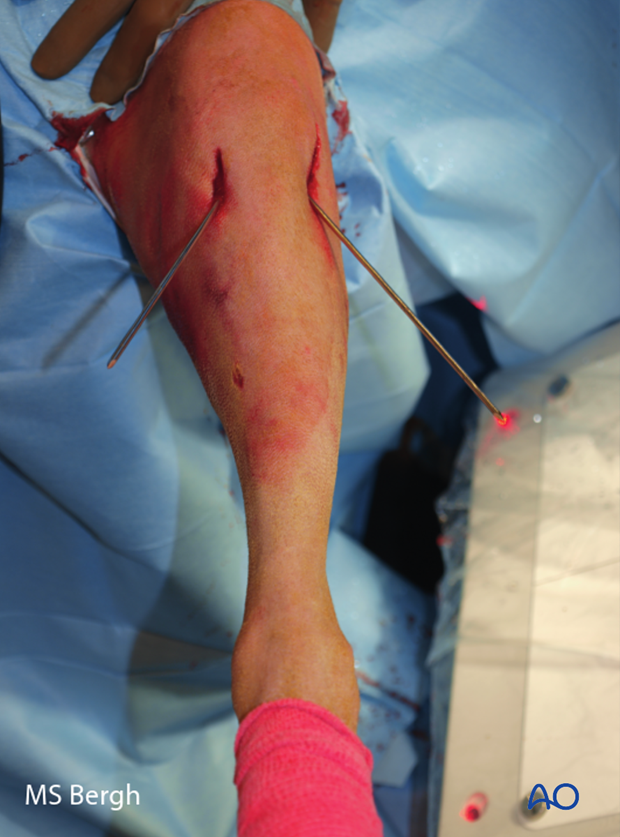

Intraoperative photo of cross pins placed percutaneously.